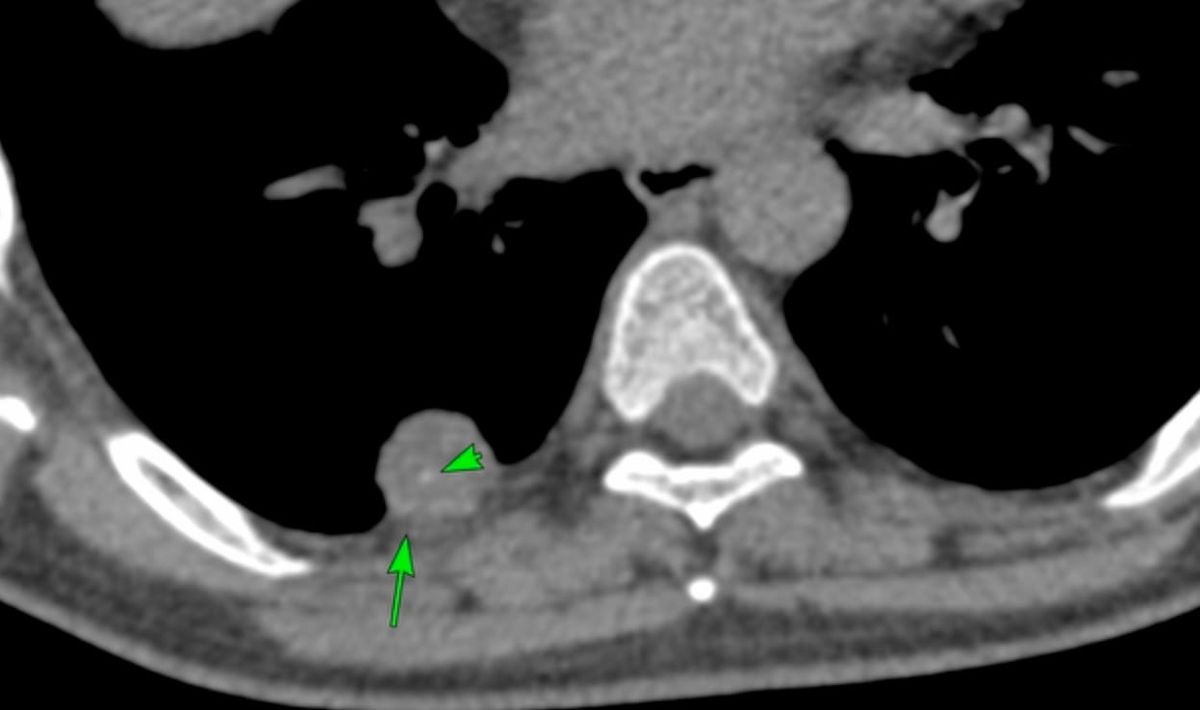

The CT scan showed extensive pleural plaques (arrows), some calcified, some not.

This is characteristic asbestos exposure related pleural disease.